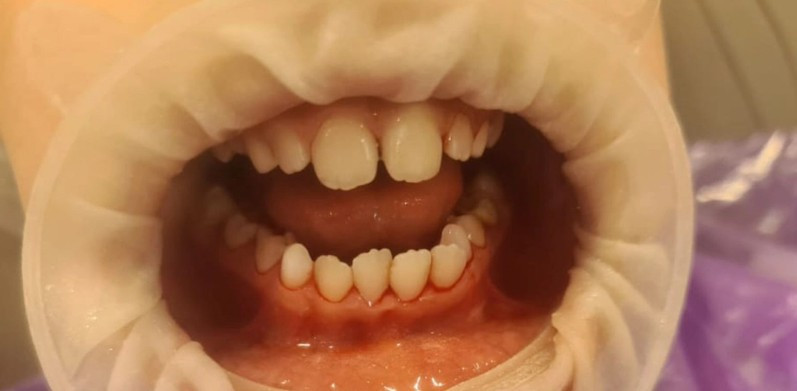

Стоматологическая клиника СКАЙДЕНТ (SKYDENT)

Профгигиена

Доктор: Попова (Михеева) Юлия Васильевна

Доктор: Новлянцева (Новосад) Екатерина Игоревна